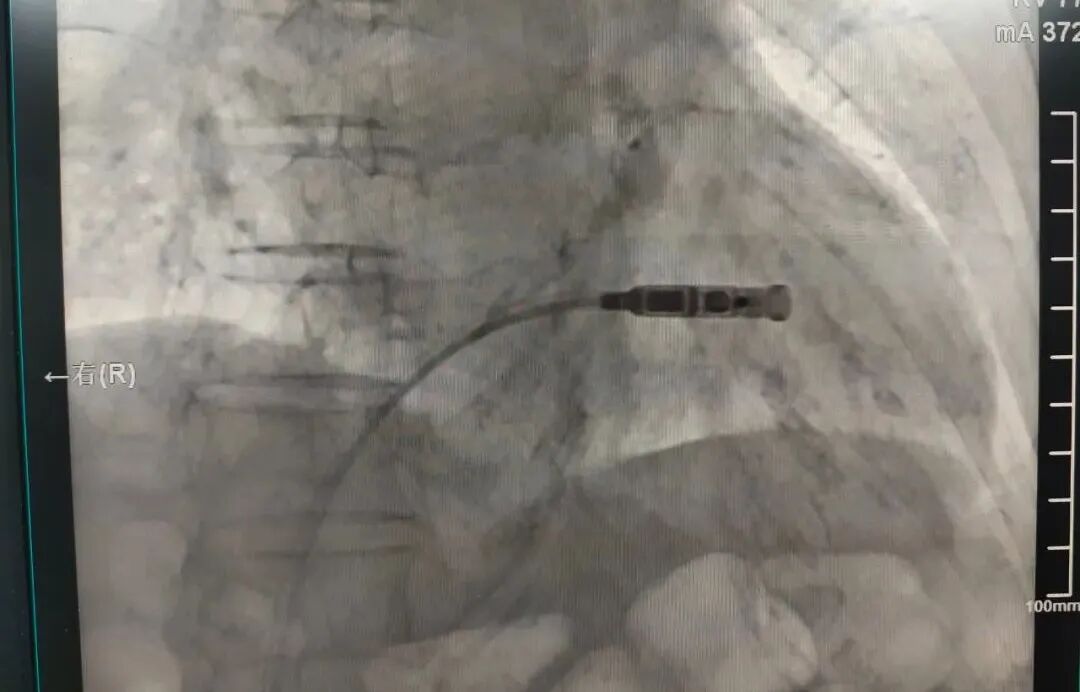

13日下午,楊飛主任帶領(lǐng)心律失常團隊為患者施行手術(shù)。在患者局部麻醉后,醫(yī)生穿刺右側(cè)股靜脈建立通路,將起搏器送入右心室,選定合適的位置,確認固定及工作參數(shù)良好,成功釋放后手術(shù)完成,用時僅1小時。整個過程中,患者始終保持清醒狀態(tài)。術(shù)后6小時拆除右股靜脈包扎繃帶,第二天即可下床自由活動。

楊飛主任手術(shù)中

Micra經(jīng)靜脈送入右心室